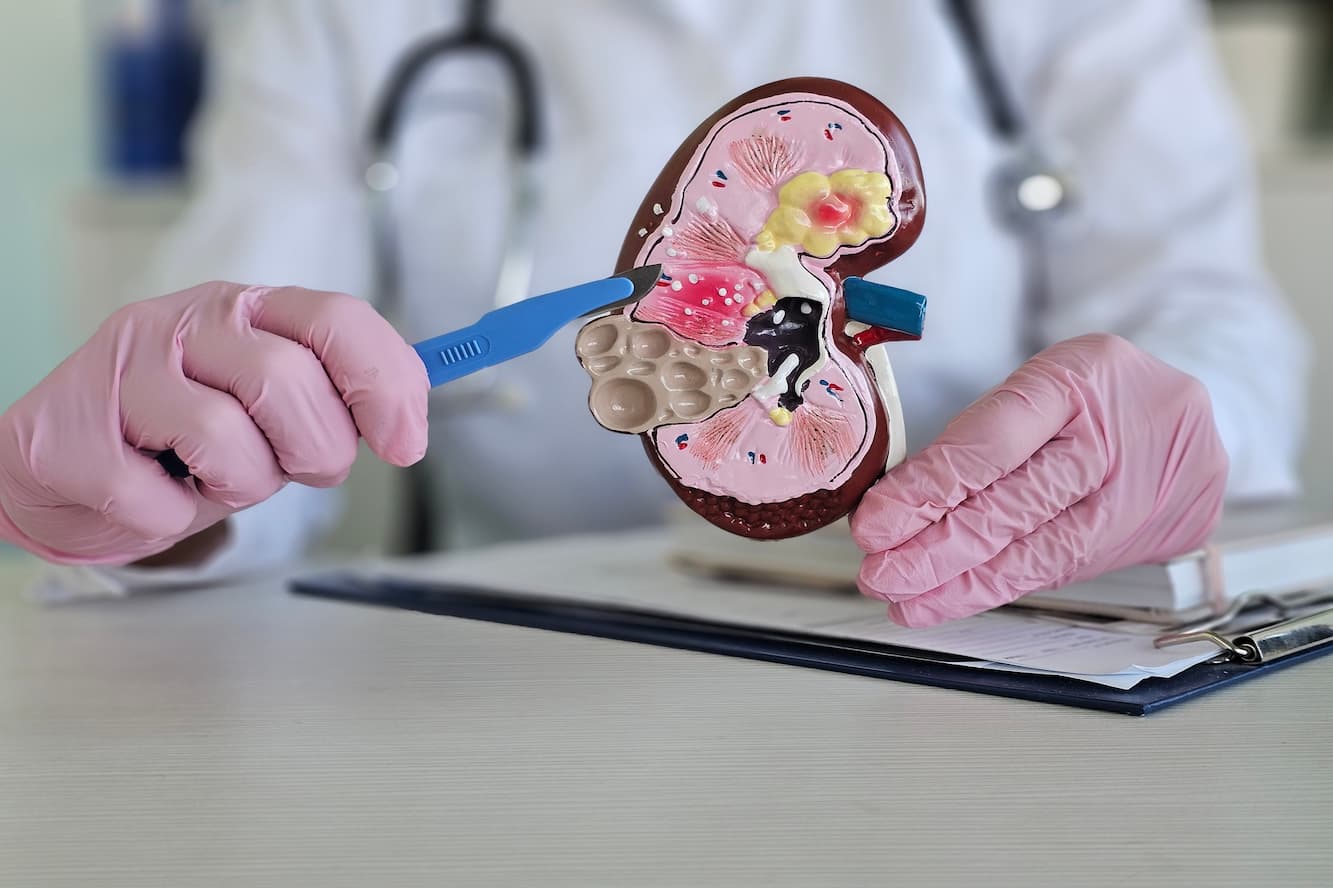

Urology is dedicated to maintaining the health of the urinary system. We work alongside esteemed urologists from our partner hospitals, who are committed to excellence and equipped with advanced technology.

Urology is dedicated to maintaining the health of the urinary system. We work alongside esteemed urologists from our partner hospitals, who are committed to excellence and equipped with advanced technology.